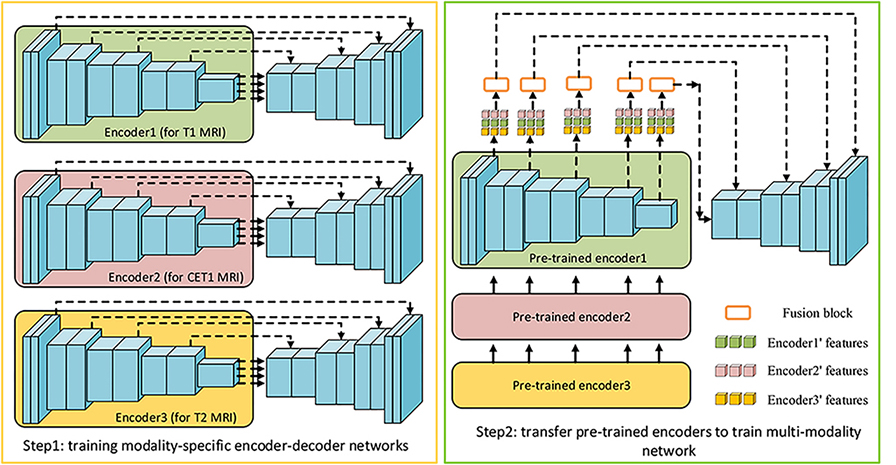

As illustrated in Figure 2, our framework is an end-to-end fully convolutional network, containing three encoders to take 3D images from three modalities of MRI as inputs. The encoder network is a VGG-liked [34] DNN, which stacks base block containing several 3D convolutional layers followed by max-pooling layers to get deeper features. And the decoder network uses 3D deconvolutional layers to upsample feature maps, the final output is a feature map with the same size as input. Both low-level features and high-level features, which are relevant to NPC segmentation, can be obtained by the design of multiple encoders and one single decoder. In order to effectively fuse low-level features from multi-modality MRI and keep balance between high-level and low-level features, a fusion block composed with 3D-CBAM and RFBlock is proposed to recalibrate and fuse multi-source low-level feature maps. For the training of network, we propose self-transfer to use pre-trained modality-specific encoders, which can capture individual modality-specific features from single modality MRI, as initial encoders of multi-modality model. The utilization of self-transfer can effectively improve the performance of encoders and make full mining of informative features from every modality of data.

3.3 Self-transfer learning

Transfer learning [40], utilizing a powerful pre-trained network as features’ extractor, is a popular trick to improve performance of new systems. Hence, using a network pre-trained in imagenet as an encoder for a segmentation network is a common operation in natural images [41, 42]. However, there is not a powerful enough 3D pre-trained model can be set as the initial features’ extractor for various 3D medical images due to their complexity and various imaging technologies. Especially for multi-modality MRI, images of each modality have their own specific imaging styles, it’s hard to obtain a features’ extractor, which can be generalized to all of them. Additionally, by the design of multi-encoder single-decoder network, complementary information and cross-modal interdependencies can be extracted, while some individual features of specific modality may be ignored. To address these problems, we propose an initialization trick named self-transfer to effectively initialize encoders and make full mining of features of different modalities of MRI. According to experimental results, performance of multi-encoder-based models can obtain considerable improvements by using self-transfer.

Specifically speaking, a modality-specific model can effectively capture individual informative features from one single modality of data, while a multi-modality model aims to obtain interdependent and complementary information from multiple-modality datasets. As a result, some individual features of one single modality may be ignored in multi-modality model. Therefore, we propose self-transfer to fully mine modality-specific features. Figure 5 is the illustration of self-transfer. The first step is to respectively train three modality-specific encoder-decoder models. Then, these pre-trained encoders will be used as the initial encoders for multi-modality model. Compared to original encoders with random initialization, these encoders have greater power to make full mining of individual features from specific modality of MRI. Meanwhile, the fusion block and decoder can effectively fuse these features to obtain informative features for final predictions. We will set several experiments to demonstrate that self-transfer can enhance the segmentation systems in the following paper.